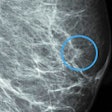

Copenhagen study confirms AI's value in breast screening